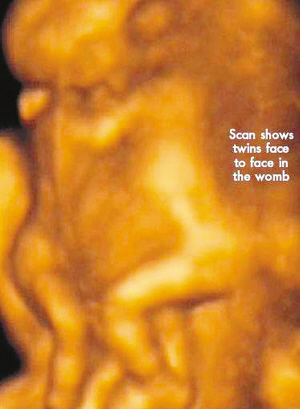

今年初,懷孕7周多的麗莎檢查發(fā)現(xiàn),懷上的竟是一對腹部緊緊相連的連體男嬰。這對連體嬰共享一只肝臟,雖然他們擁有各自的心臟,但兩顆心臟卻粘連在了一起。醫(yī)生建議麗莎立即接受流產(chǎn)手術(shù),他認(rèn)為麗莎腹中的連體嬰甚至無法活到她懷孕10周的時候。

麗莎每周都要到醫(yī)院接受醫(yī)學(xué)掃描,而她腹中的連體嬰也讓醫(yī)生感到驚訝不已,因為他們已經(jīng)打破了醫(yī)生的死亡預(yù)言,一直在母親子宮中堅強活到了現(xiàn)在。麗莎將于兩周內(nèi)接受剖腹產(chǎn)手術(shù)。